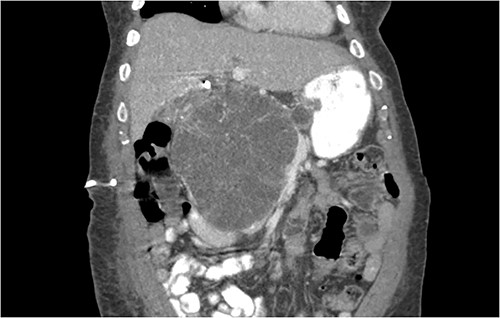

Another abdominal CT was performed redemonstrating the large heterogenous mixed attenuating mass within the right abdomen measuring 14.0 × 10.0 × 13.0 cm likely originating from the pancreatic head with resultant displacement of the PTC anteriorly and to the right with extensive pancreatic ductal dilation (Figs 2 and 3).

Coronal CT showing a large heterogeneous mass in the pancreatic head with typical honeycomb feature.

Mass effect to abdominal viscera from the 14 × 10 × 13 cm pancreatic head mass.

The mass extended up into the base of the liver, effaced the portal and superior mesenteric veins (SMV) (Fig. 4), and displaced the hepatic and superior mesenteric arteries.